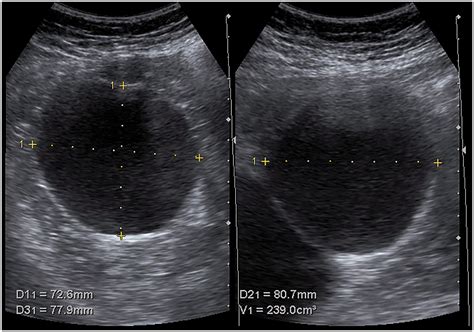

Because symptoms can overlap with other conditions like gallstones or gastric issues, diagnostic imaging is the gold standard for confirming that a patient is suffering from Symptomatic Liver Cysts. Doctors typically rely on:

Ultrasound Initial screening tool to detect fluid-filled sacs.